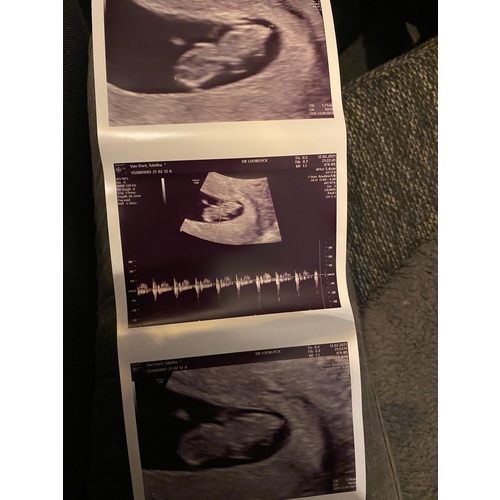

Dit is een echo van 7w wel niet de mijne is van een app. De echo is inwendig en je zal normaal een kloppend hartje zien.

Wow dat is mooi helder! Is dat via de VK of het ziekenhuis? Ik mag vanmiddag voor de eerst echo met 7 weken. Heel spannend! 馃グ